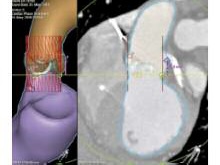

Мультиспиральная компьютерная томография (МСКТ) аорты. Выраженный кальциноз трехстворчатого АК. Размер фиброзного кольца АК 24¥28 мм, диаметр аорты на уровне синусов Вальсальвы 32 мм. Устья коронарных артерий расположены выше 10 мм от плоскости фиброзного кольца АК (рис. 4).

Рис. 4. МСКТ-аортография.